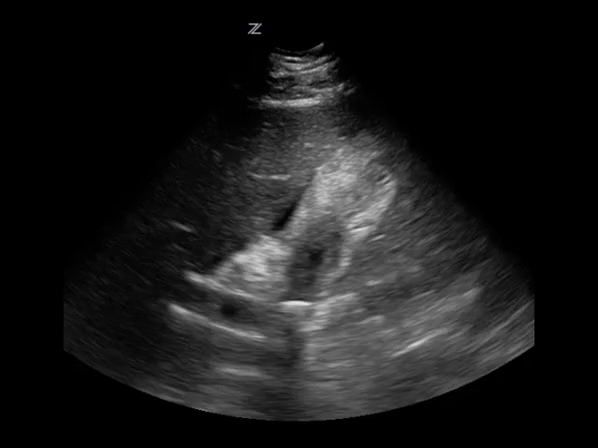

Увеличенный желчный пузырь выявляется при пальпации области правого подреберья – определяется болезненное либо безболезненное округлое образование. Однако, пальпация не позволяет установить точные размеры органа, особенно у ребенка. Поэтому обязательно проводится инструментальная диагностика. Обнаружить отклонения в размерах органа и выявить функциональные нарушения его работы можно с помощью УЗИ.

Ультразвуковое исследование – информативный метод, позволяющий поставить точный диагноз. При этом УЗИ является самым безопасным способом диагностики, при необходимости его можно проводить даже для обследования новорожденного.

С помощью УЗИ помимо увеличения размеров органа можно обнаружить:

- утолщение либо истончение стенок, включения в просвете желчного пузыря (обычно при холецистите и жкб);

- нарушение сократительной способности органа (при дискинезии желчевыводящих протоков);

- сужение или перекручивание желчных протоков, перегиб шейки пузыря (у детей, как правило, обусловлены врожденными структурными аномалиями, у взрослых чаще являются приобретенными);

- расширенный общий желчный проток (отмечается при жкб и стенозирующем папиллите);

- растяжение пузыря, утолщение его стенок свыше 5 мм, жидкость внутри органа (обнаруживаются при эмпиеме – скоплении в полости желчного пузыря большого количества гнойного содержимого);

- растяжение без утолщения стенок, жидкость внутри (развиваются при мукоцеле – слизистой кисте);

- обструкция желчевыводящего протока, утолщение стенок пузыря (может свидетельствовать о глистной инвазии, когда гельминты перекрывают желчный проток, препятствуя оттоку желчи либо о воспалении головки поджелудочной железы, при этом утолщение стенок пузыря может быть признаком нагноения);

- доброкачественное или злокачественное образование, полипы.

Острый калькулезный холецистит на УЗИ

Острый калькулезный холецистит — это воспаление желчного пузыря по вине желчных камней.

Центральная задача УЗИ — отличить катаральную и деструктивную форму острого холецистита.

При катаральном воспалении стенка диффузно утолщена, перипузырный жир эхогенный (отек).

При деструктивной форме толстая стенка с дефектами, в просвете слизистые псевдомембраны.

При перфорации дефект стенки сквозной, вокруг пузыря разливается жидкость, нередко камни.

Диагноз острый калькулезный холецистит устанавливают лишь располагая системой признаков:

- Вколоченный конкремент в шейке желчного пузыря или пузырном протоке нарушает отток;

- Желчный пузырь раздутый, продольный размер >120 мм, а передне-задний размер >40 мм;

- Толщина стенки >3 мм, двойной контур, слоистая структура или диффузная неоднородность;

- В ямке желчного пузыря высокой эхогенности околопузырный жир и анэхогенная жидкость;

- Положительный симптом Мерфи, если при давлении датчика на дно пузыря усиленная боль.

Острый калькулезный холецистит: вколоченный конкремент шейки бросает заднюю тень.